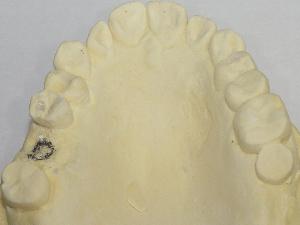

STEP1 カウンセリングと検査

STEP2 診断に基づいた治療計画の説明